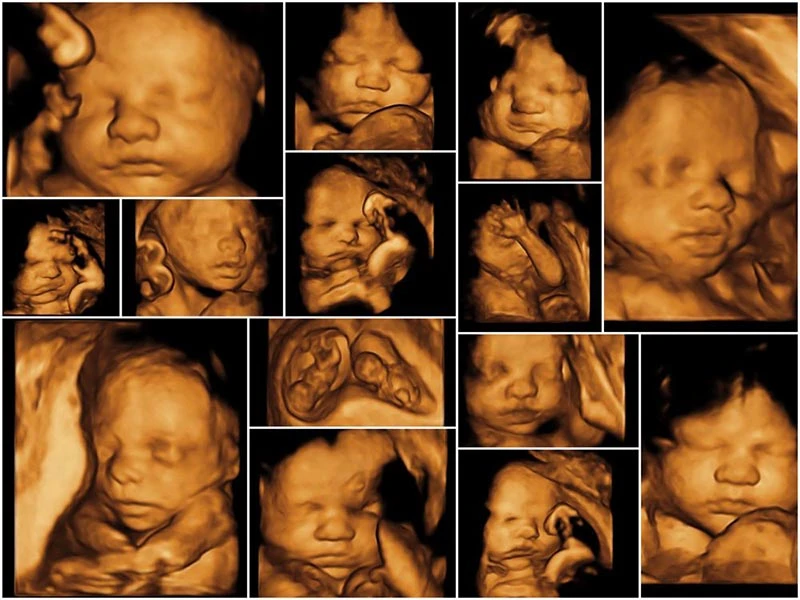

Việc so sánh các loại siêu âm thai giúp các bậc phụ huynh hiểu rõ hơn về sự khác biệt cũng như lợi ích riêng của từng kỹ thuật về cả mặt chẩn đoán lẫn trải nghiệm. Siêu âm hình thái và siêu âm 4D là hai trong số những phương pháp phổ biến nhất, mỗi loại mang lại những thông tin cụ thể khác nhau cho việc theo dõi sự phát triển của thai nhi. Trong khi siêu âm hình thái tập trung vào việc đánh giá chi tiết cấu trúc, sự phát triển của các cơ quan bên trong thai nhi để phát hiện dị tật, thì siêu âm 4D lại đưa đến những hình ảnh sống động, rõ nét và chân thực về em bé.

Ngược lại, siêu âm 4D, thường được tiến hành từ tuần 24 đến 32 thai kỳ, nổi bật với khả năng tạo ra hình ảnh trong không gian ba chiều và cho phép quan sát chuyển động của em bé trong bụng mẹ theo thời gian thực. Điều này không chỉ đem lại trải nghiệm thú vị mà còn giúp các bậc phụ huynh nhìn thấy cử động, như là những cái nhăn nhó, cười, hay mút tay của con yêu, tạo ra sự kết nối tình cảm đặc biệt với thai nhi trước khi bé chào đời.

Điểm khác biệt lớn nhất giữa hai loại siêu âm này chính là mục tiêu và khả năng cung cấp thông tin chi tiết. Trong khi siêu âm hình thái nhấn mạnh vào khía cạnh y tế, giúp phát hiện và xử lý các dị tật bẩm sinh, thì siêu âm 4D lại tập trung vào việc tạo ra trải nghiệm trực quan, rõ nét cho cha mẹ. Do đó, lựa chọn giữa hai loại này thường phụ thuộc vào nhu cầu và hoàn cảnh cụ thể của từng thai kỳ cũng như lời khuyên từ các bác sĩ chuyên khoa.

Cả hai phương pháp đều có vai trò đặc biệt và quan trọng trong việc theo dõi sự phát triển của thai nhi. Việc kết hợp đúng đắn giữa siêu âm hình thái và 4D giúp các bậc phụ huynh không những đảm bảo sức khỏe của con từ trong bụng mẹ mà còn mang lại những khoảnh khắc đáng nhớ trong hành trình chào đón bé yêu.